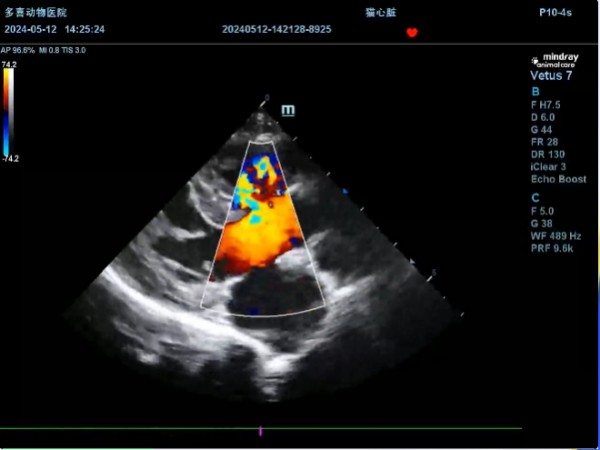

② 超声心动图:确诊金标准,通过二维超声可直接显示室间隔缺损的位置、大小;彩色多普勒超声可清晰观察分流方向与流速,同时评估心室壁厚度、肺动脉压力及瓣膜功能。

(视频内可见穿过室间隔出现马赛克血流,主要颜色也是红色,为靠近探头的方向,是左向右分流)